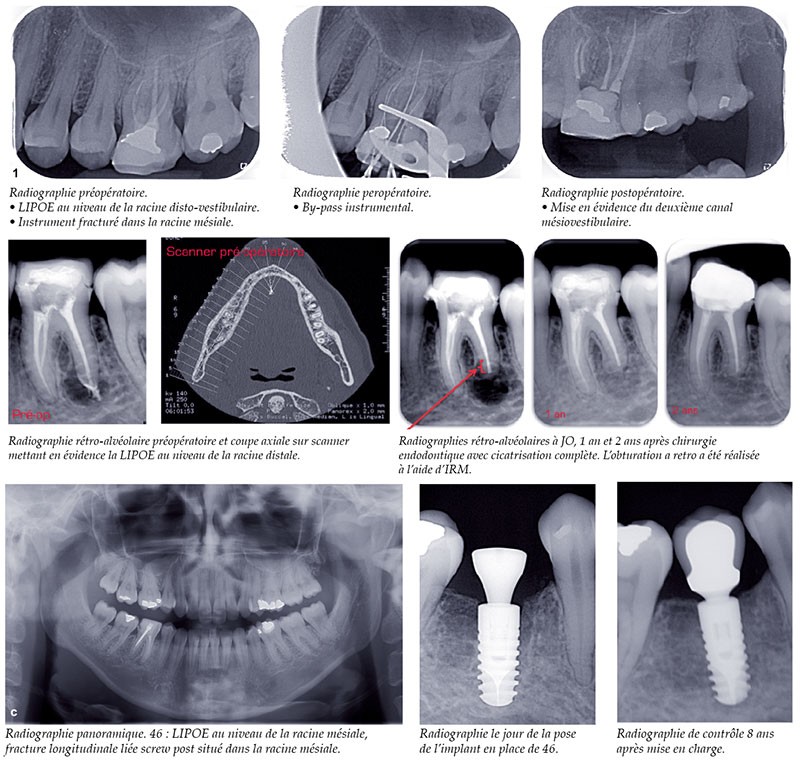

Les thérapeutiques endodontiques et implantaires ont un objectif commun : permettre une restauration fonctionnelle et esthétique ayant la pérennité la plus longue possible. L’apparition et le développement des thérapeutiques implantaires depuis 50 ans ont constitué indéniablement un changement dans les mentalités des chirurgiens-dentistes et les possibilités de traitements offertes aux patients. Il est admis que la meilleure solution pour le remplacement d’une dent unitaire absente est une solution implantaire. Mais, qu’en est-il d’une dent présente, traitée endodontiquement avec un échec clinique et/ou radiologique (fig. 1) ?